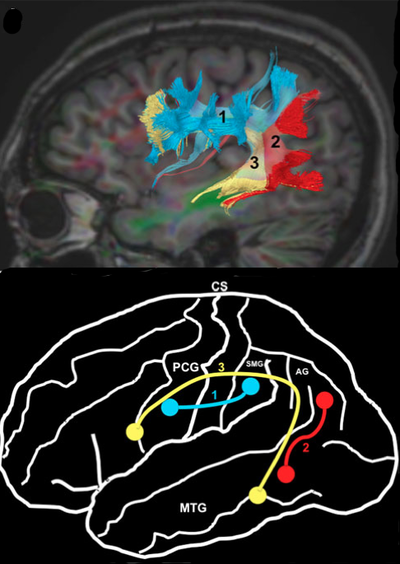

Fasciculus Longitudinalis Superior & Fasciculus arcuatus

Fasciculus arcuatus (AF) som er en delkomponent af Fasciculus Longitudinalis Superior (SLF) (Fig.1), blev først beskrevet af Reil & Autenrieth i begyndelsen af det 19. århundrede, som et dybt liggende fiberbundt som forbinder frontal, temporal og parietal regionerne. Fasciculus Arcuatus buer sig rundt om lateral fissuren, og rundt om Insula (Insula of Reil). Det er den samme anatom Johan Christian Reil. I de senere år er der lavet mange studier af SLF og AF dels med DTI tractografi studier med MR-teknologi, dels med dissektionsstudier med Klinger teknik. Ved Klinger teknik formalin fikseres hjernen, og fryses derefter. Der dannes små iskrystaller i vævet som gør det muligt efterfølgende af dissekere de forskellige baner i hvid substans fra hinanden.

AF kan inddeles i tre komponenter som det fremgår af Fig. 1, den dybest beliggende og længste AF og to kortere mere overfladisk beliggende komponenter, henholdsvis det anteriore og det posteriore segment af SLF.

AF har et forløb rundt om Insula på niveau i dybden med Sulcus Limitans eller Sulcus Circularis, den sulcus der adskiller Insula fra henholdsvis temporal-, parietal- og frontallappen. Det anteriore & posteriore segment af SLF ligger superficielt, altså lateralt for AF, og vil således ved kirurgi mødes før AF.